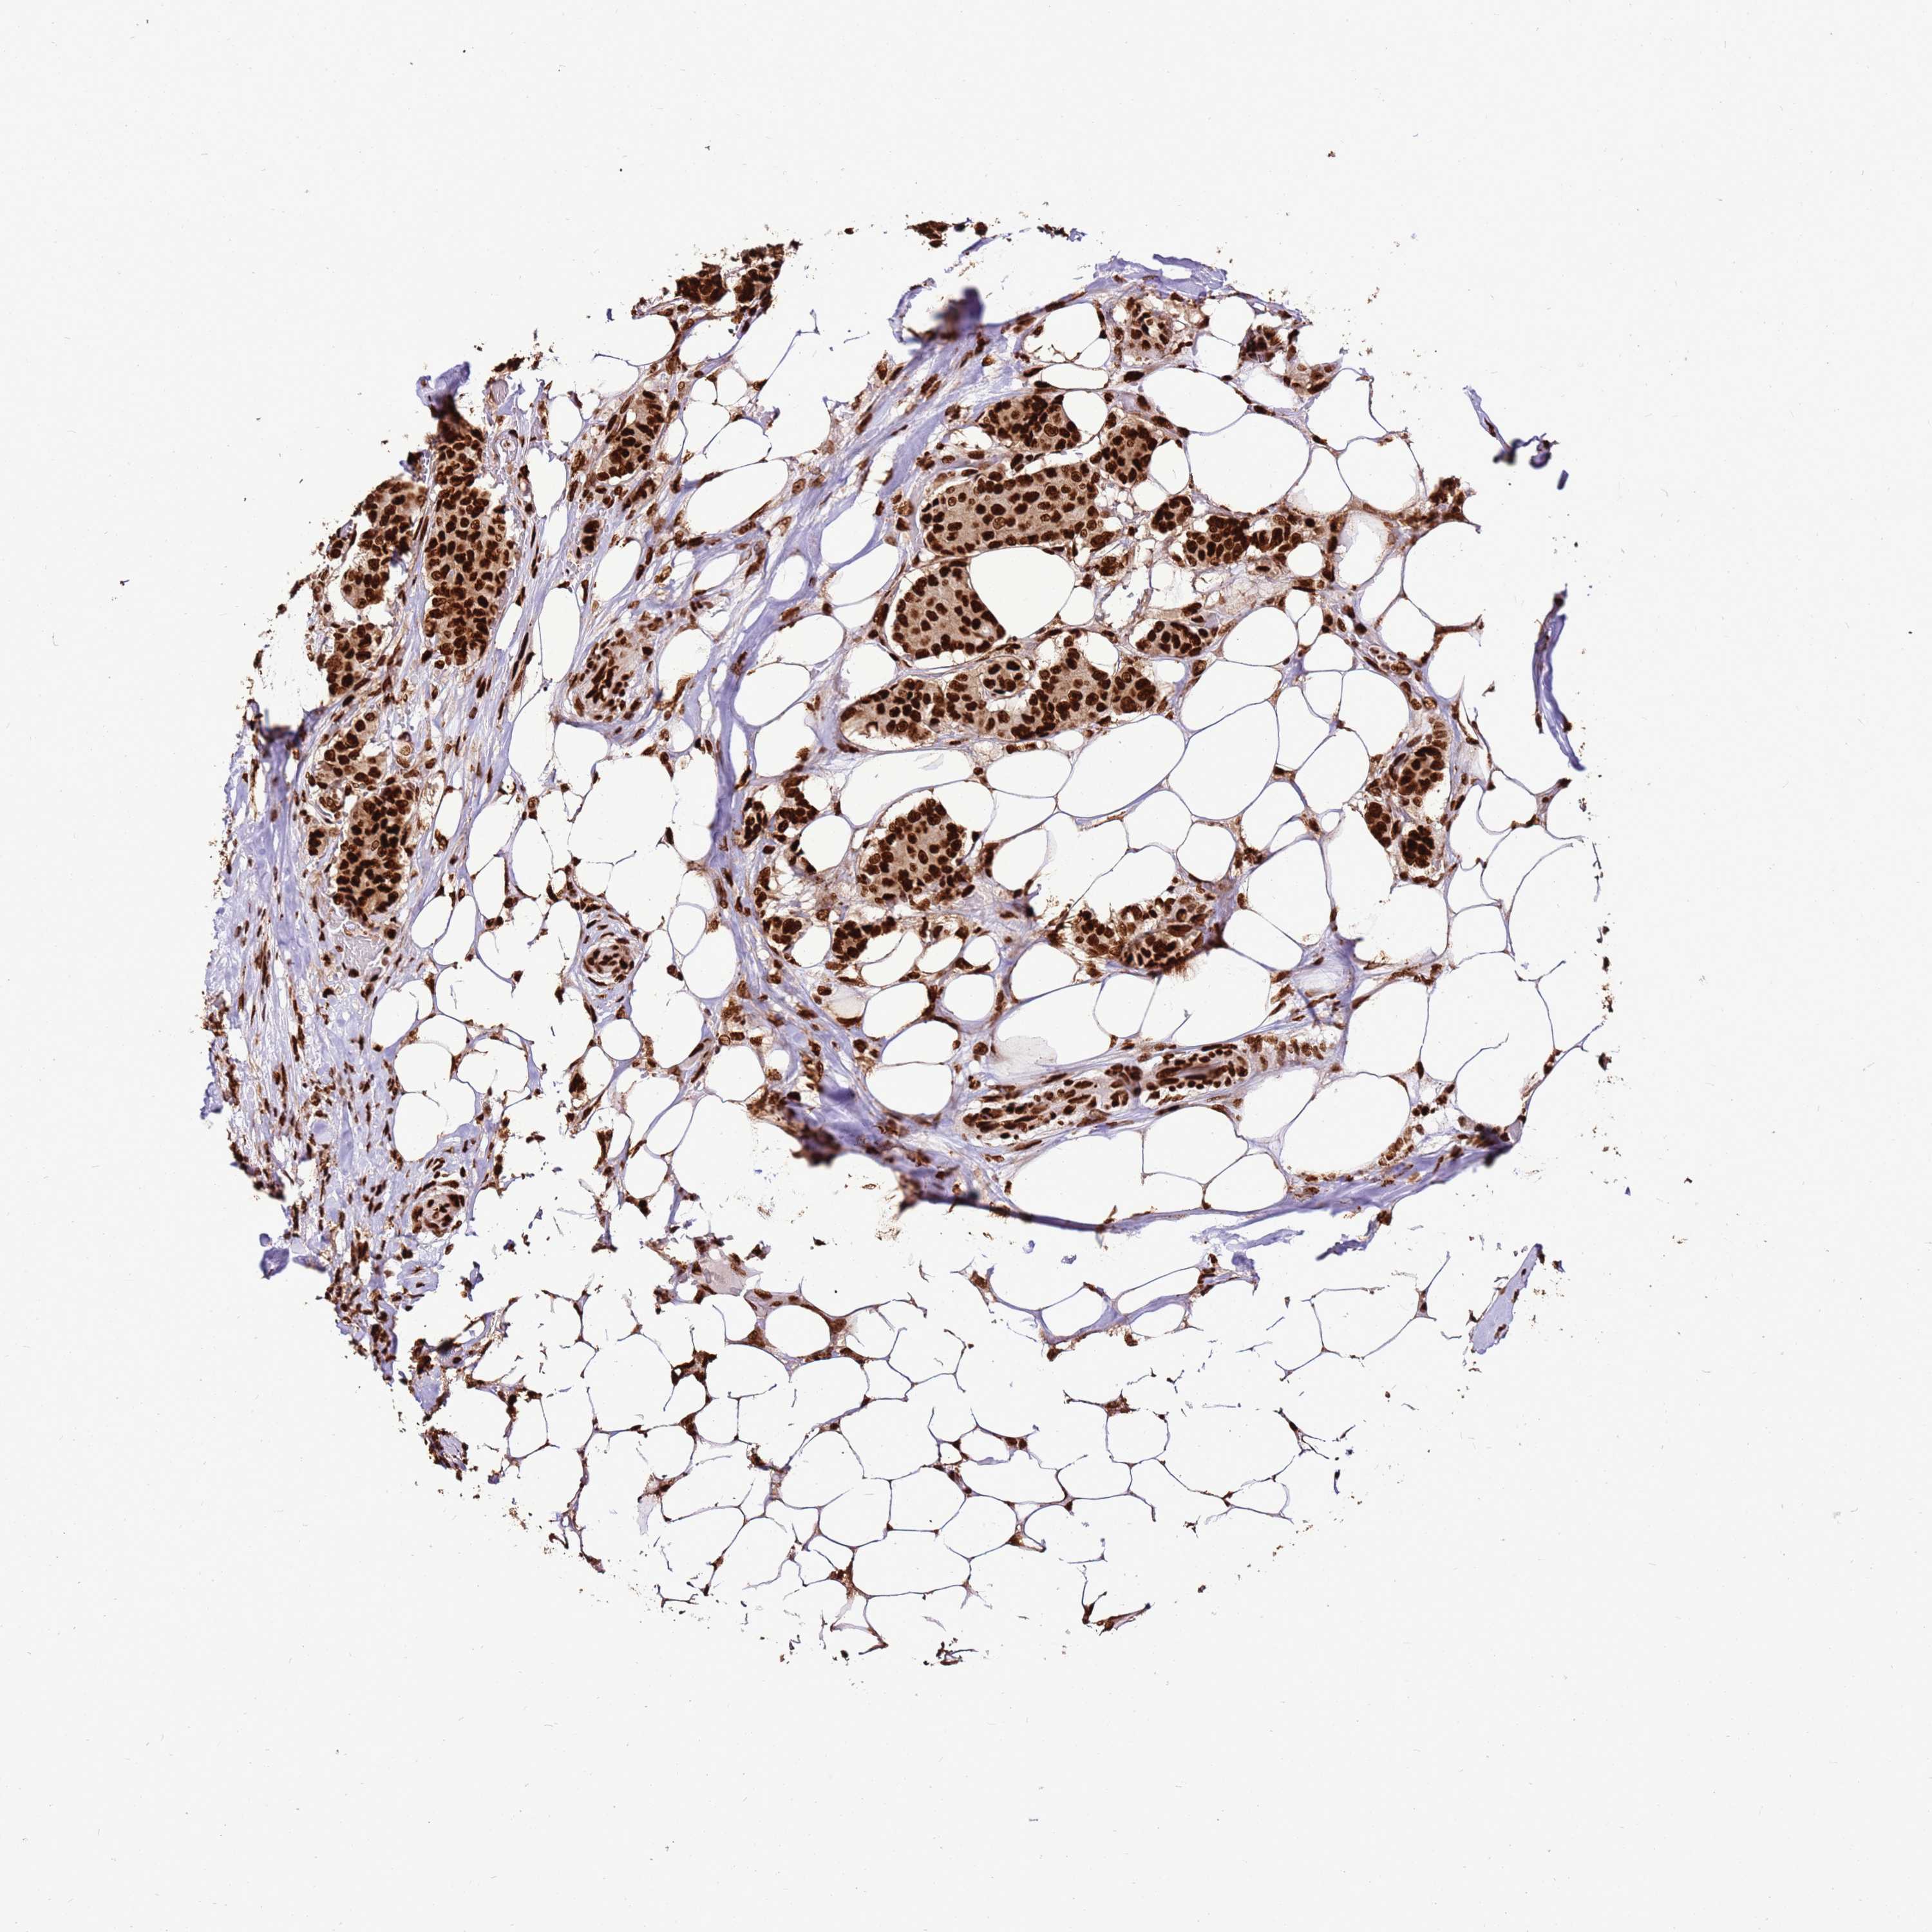

CANCER BREAST CANCER Show tissue menu

BRCA TCGA BRCA VALIDATION PROTEIN EXPRESSION